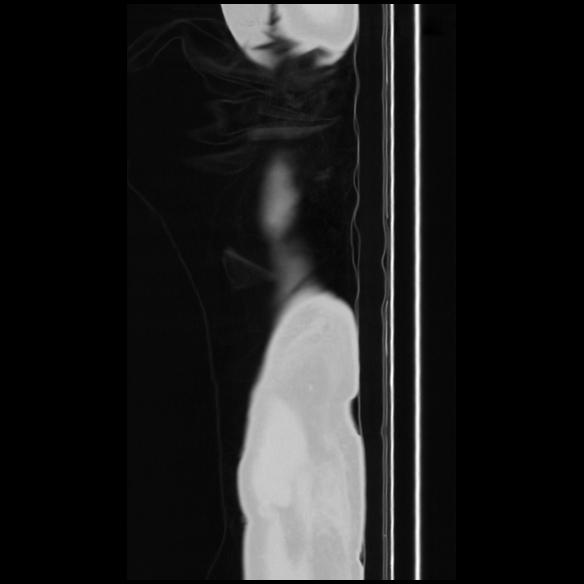

7 CUERPO,CE,Sagittal,3.000,CUERPO,Sagittal,